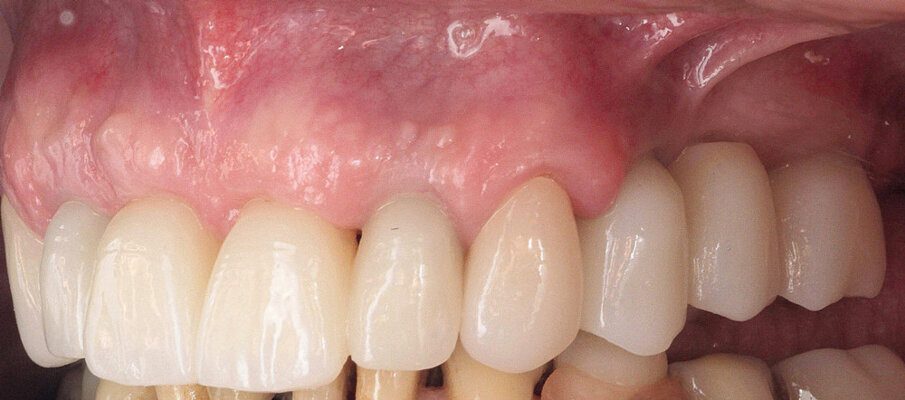

Definitivni protetski rad napravljen je nakon što je završila faza oseointegracije implantata s tri monolitna mosta od cirkonijevog dioksida (DD CubeX, Dental Direkt) proizvedenih CAD/CAM postupkom. Mostovi su pomoću vijaka pričvršćeni na titanske abutmente (PS TiB, BEGO Implant Systems) (Slike 14–16). Pravilan dosjed protetske nadogradnja se nakon umetanja potvrdio rendgenskom snimkom (Slika 17.). Kontrolni pregled nakon dvije godine u srpnju 2019. pokazao je izvrsno estetsko i kliničko stanje mekog tkiva (Slike 18–20). U području implantata radiografski se nije mogao utvrditi gubitak krestalne kosti (Slika 21.). Oba korijena središnjih sjekutića koji su ostavljeni u alveoli kao ni distobukalni korijen zuba 26 nisu pokazali nikakve znakove periapikalne upale. Pacijentica nije imala nikakvih pritužbi, a oralna higijena značajno se poboljšala tijekom razdoblja praćenja.

Slika 14. Frontalni prikaz definitivne protetske nadogradnje. Odnosi pokazuju dobru estetiku bez znakova komplikacija mekih tkiva Slika 15. Pogled na definitivni rad s desne strane. Slika 16. Pogled na definitivni rad s lijeve strane. Slika 17. Završna rendgenska slika s definitivnim implanto protetskim radom in situ. Slika 18. Frontalni prikaz definitivnog protetskog rada nakon dvogodišnjeg praćenja. Slika 19. Prikaz definitivnog protetskog rada s lijeve strane nakon dvogodišnjeg praćenja. Slika 20. Prikaz definitivnog protetskog rada s desne strane nakon dvogodišnjeg praćenja.